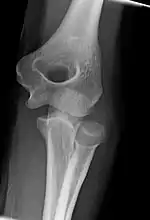

Right: AP X ray of a dislocated right elbow

The types of disease most commonly seen at the elbow are due to injury.

Fractures

There are three bones at the elbow joint, and any combination of these bones may be involved in a fracture of the elbow. Patients who are able to fully extend their arm at the elbow are unlikely to have a fracture (98% certainty) and an X-ray is not required as long as an olecranon fracture is ruled out.[27] Acute fractures may not be easily visible on X-ray.[28]

Dislocation

Elbow dislocations constitute 10% to 25% of all injuries to the elbow. The elbow is one of the most commonly dislocated joints in the body, with an average annual incidence of acute dislocation of 6 per 100,000 persons.[30] Among injuries to the upper extremity, dislocation of the elbow is second only to a dislocated shoulder. A full dislocation of the elbow will require expert medical attention to re-align, and recovery can take approximately 8–14 weeks.